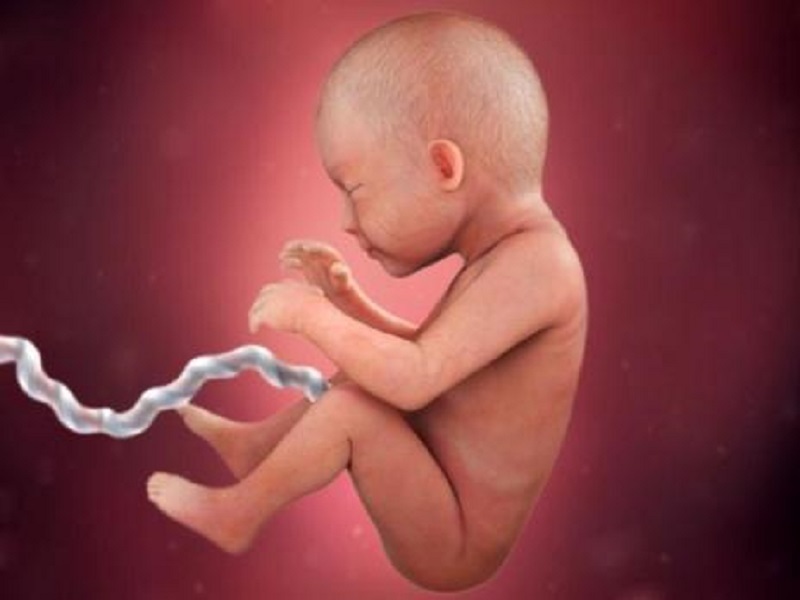

آمار افزایشی سقط جنین در کرمانشاه ادامه دارد

به گزارش خبرنگار تابناک کرمانشاه، رضا منصوری روز گذشته دوشنبه (دهم اردیبهشت ماه) در نشست خبری با اصحاب رسانه که در سالن جلسات سازمان بسیج جامعه پزشکی استان کرمانشاه برگزار شد، اظهار کرد: نرخ رشد جمعیت در ۳۰ سال گذشته ۳.۹ درصد بوده که در حال حاضر در کشور به هفت دهم درصد و در استان کرمانشاه به ۰.۶ درصد رسیده است.

وی افزود: در صورت جلوگیری از حتی ۳۰ درصد سقط جنین در کشور سالانه ۱۵۰ هزار نفر به موالید کشور اضافه میشود، لازم است که تمامی دستگاههای مرتبط برای مقابله با سقط جنین پای کار بیایند.

رئیس بسیج جامعه پزشکی استان کرمانشاه تصریح کرد: راه مقابله با سقط جنین در حال حاضر ضروریتر است، زیرا تصحیح فرهنگ فرزندآوری به افزایش جمعیت کمک شایانی میکند.

وی در خصوص طرح «نفس» تشریح کرد: با توجه به شبکه سازی صورت گرفته با دستگاههای مرتبط شامل ماماها، بیمارستانها و سایر مراکز شناسایی مادرانی که قصد سقط جنین دارند صورت گرفته و به آنها مشاورههای لازم داده میشود.

منصوری اضافه کرد: از ابتدای شروع این طرح در فروردین سال ۱۴۰۲ بیش از ۵۰ مادر در سال گذشته تحت مشاوره قرار گرفتند که در نتیجه ۴۳ نفر از آنها از انجام سقط جنین منصرف شدند و در صورت تداوم این طرح قطعاً با کاهش آمار سقط جنین مواجه خواهیم بود.

رئیس بسیج جامعه پزشکی استان کرمانشاه ابراز کرد: مسائل مالی تنها بحث مورد نظر برای انجام سقط جنین توسط مادران نبوده و عوامل دیگری مانند بارداری برنامهریزی نشده، جنسیت و عوامل فرهنگی از جمله دلایل انجام این کار هستند.